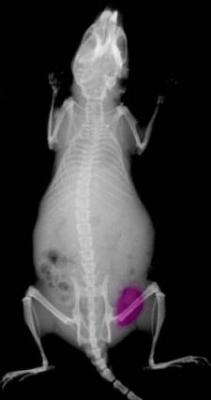

In an organism, the KODAK X-SIGHT Dyes can illuminate a region of interest when excited by the appropriate wavelength of fluorescent light, thus allowing the researcher to visualize their target. While the KODAK X-SIGHT Imaging Agents have been optimized for KODAK Image Station and In-Vivo Systems, they are also compatible with other commercially available digital imaging systems.